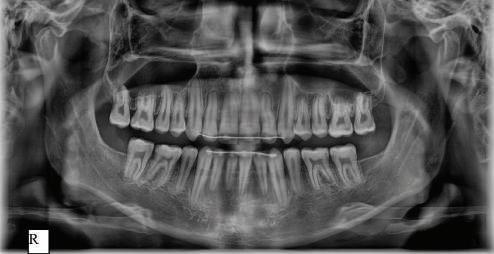

Dental Tribune Bulgarian Edition / октомври 2022 г.16 клиничен случай с алайнери Г орният латерален ре зец е вторият найчесто вродено липсващ зъб.1,2 Поради разполо жението му във видимата зона на усмивката лечение то на подобни случаи нала га мултидисциплинарен под ход, целящ отличен функцио нален и естетичен резултат. Налице са няколко лечебни мо далности, свързани с различ но разпределение на място то: първият вариант е орто донтско отваряне на място и възстановяване на липсва щия зъб с конструкция, под държана от съседните зъби3 или от имплант4, докато при втория подход разстоянията се затварят и премоларът заема мястото на канина.5 Изборът на лечебен подход трябва да бъде направен съв местно от зъболекар и паци ент въз основа на очакванията на последния и предвиди мостта на лечението. Множе ство фактори влияят върху това решение, като напри мер типа малоклузия, размера, формата и цвета на кучеш ките зъби6, оклузалните вза имоотношения (овърджет и овърбайт), лицевия профил, дължината на зъбната дъга и несъответствията в разме ра на зъбите.7 В настоящата публикация се разглежда случаят на жена в зряла възраст с вродена лип са на горен ляв латерален резец. Бяха приложени про зрачни алайнери за отваряне на място за единичен им плант и бяха постигна ти функционална оклузия и отлична естетика. ПРЕДСТАВЯНЕ НА СЛУЧАЯ Диагноза Пациентката бе на 32 годи ни, когато лечението започна, и първоначалното ѝ състоя ние бе следното (фиг. 1–3): липсващ горен ляв латерален резец; клас II, подклас I малоклузия; отклонение на горната сре динна линия вляво; Доклад на клиничен случай ЛЕЧЕНИЕ С АЛАЙНЕРИ НА ПАЦИЕНТ С АГЕНЕЗИЯ НА ЛАТЕРАЛЕН РЕЗЕЦ Д-р Iro Eleftheriadi и д-р Christodoulos Laspos, Гърция и Кипър Фиг. 1a–h Предоперативни лицеви и интраорални снимки. Фиг. 2a–e Дигитални модели преди началото на лечението. Фиг. 3 Панорамна снимка преди лечението. Фиг. 1a Фиг. 1d Фиг. 1f Фиг. 2a Фиг. 2d Фиг. 2b Фиг. 2e Фиг. 3 Фиг. 2c Фиг. 1b Фиг. 1e Фиг. 1g Фиг. 1h Фиг. 1c

Dental Tribune Bulgarian Edition / октомври 2022 г. 17клиничен случай с алайнери леко струпване в долната че люст; несъответствие по Болтън (мандибуларен излишък от 3.06 мм във фронталната зона и общо 1.47 мм); издължено лице с лицева аси метрия; конвексен профил с ретруди рана долна челюст и проми нентен нос. На мястото на зъб #46 бе на лице имплант, а зъби #16 и 26 са ендодонтски лекувани. Тези зъби бяха асимптоматич ни, затова бе взето решение да се прави релечение само при нужда. Мъдреците липсваха. Анализът на телерентгеногра фията (фиг. 4) показа ретрог натна мандибула (SNB: 74.2°) и нормална инклинация на резците както в